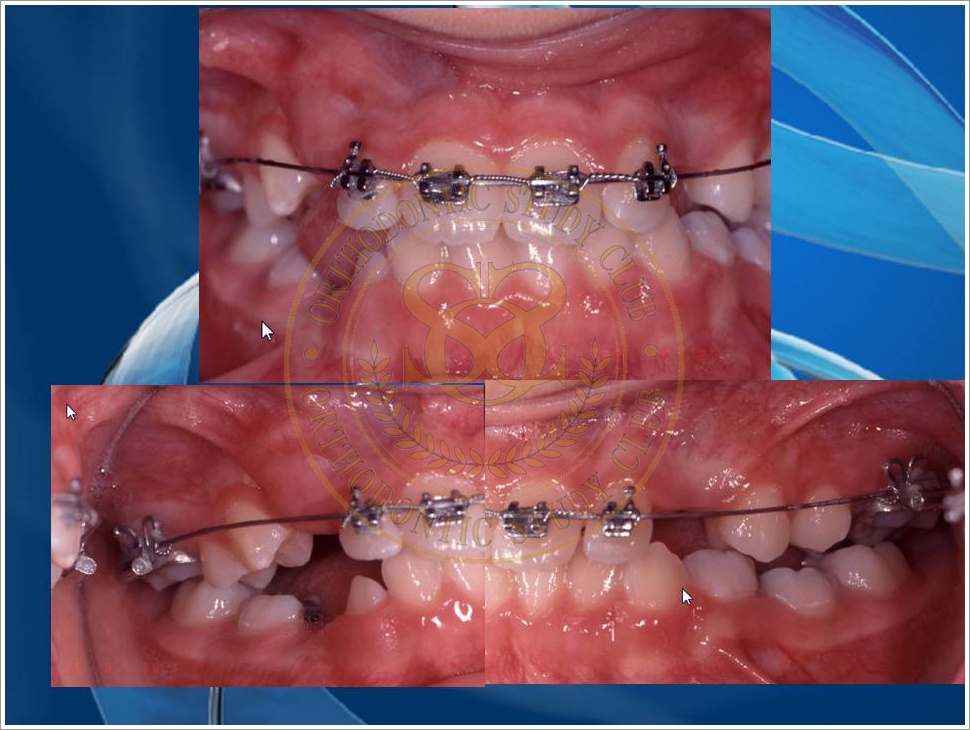

Treatment of Pseudo Class III (Class I Molar Relationship) and management of the embedded maxillary canine (Pt. Miss J.I.)